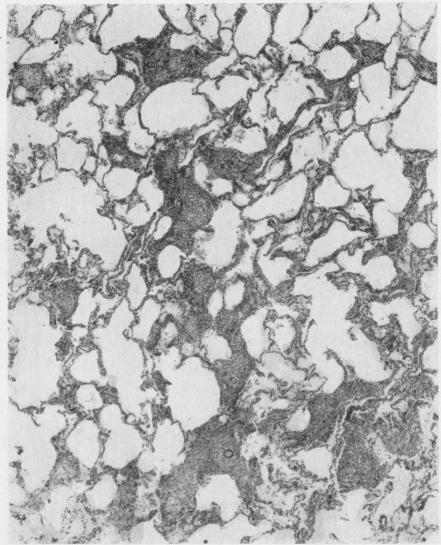

A histological study of the lungs in 52 cases of chronic beryllium disease.

Br J Ind Med. 1958 Apr;15(2):84-91. doi: 10.1136/oem.15.2.84.